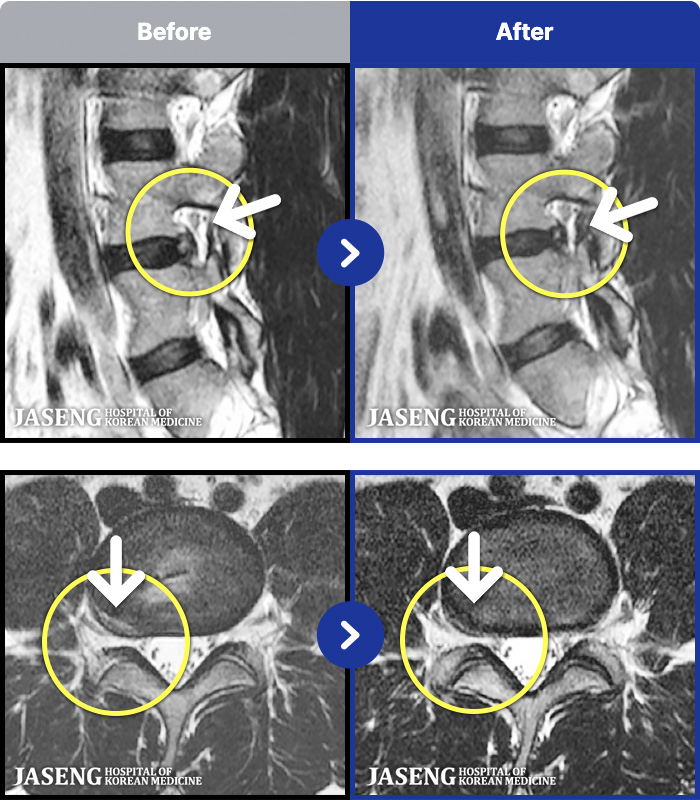

- MRI ġ

MRI ġ

1,240 MRI ũ ʸ Ȯϼ.